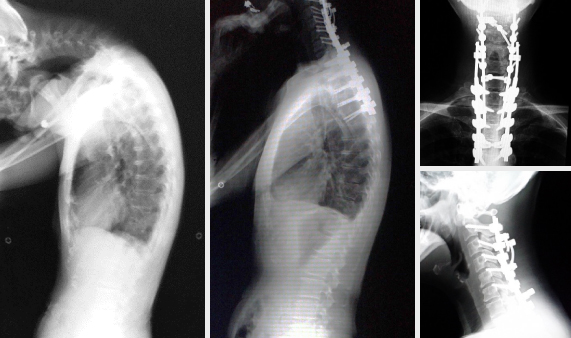

Corrective surgeries for spinal deformity

We achieved high correction ration by corrective surgeries for spinal deformity, such as adolescent idiopathic scoliosis and adult spinal deformity. We commonly perform pedicle screw instrumentation, growing rod technique for infant scoliosis, and spinal osteotomy for adult spinal deformity. Our study to identify genetic factor of adolescent idiopathic scoliosis has been published in Nature Genetics in 2012.

We perform cervical spine instrumentation for cervical spinal diseases such as myelopathy due to cervical instability, kyphotic deformity and drop head syndrome. With this technique, we can achieve better clinical results for those diseases compared to spinal cord decompression alone.